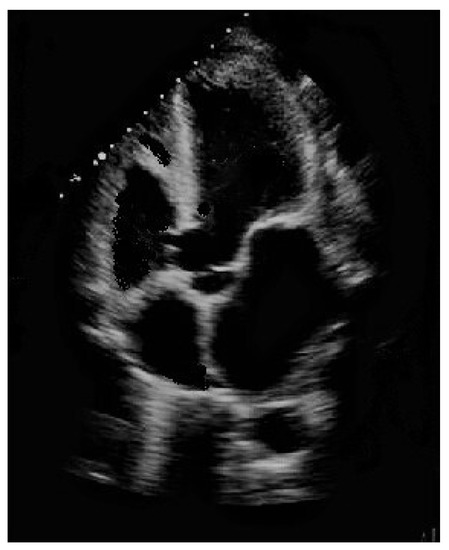

Ventricular septal defect, manifested either as an isolated event or in conjunction with other cardiac abnormalities in syndromic and non-syndromic patients, is by far the most frequently encountered congenital heart defect (CHD) after bicuspid aortic valve in clinical practice, accounting for approximately 20% of all diagnoses when isolated [1,2]. Numerous classifications for ventricular septal defects have been proposed, although it is indisputable that perimembranous ventricular septal defect is the most frequently observed subtype in children (Figure 1), whilst a muscular presentation is most common in newborns.

Figure 1. Perimembranous ventricular septal defect partially occluded by tricuspid valve accessory tissue.